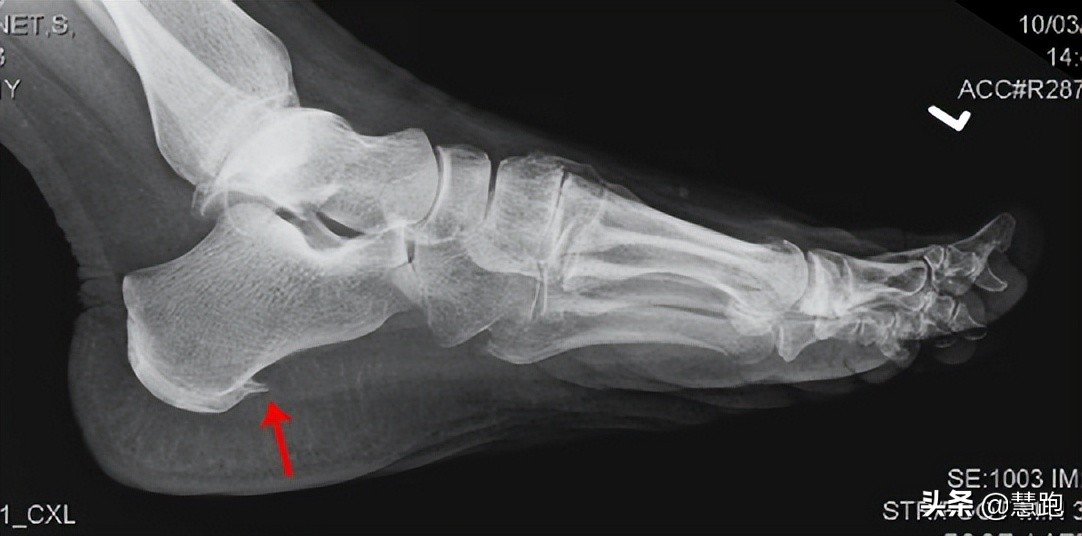

有跑者到医院检查,拍片后显示有跟骨骨刺(专业术语称为跟骨骨赘),大惊失色,会认为足底长出骨刺自然戳着疼。其实,骨刺不是导致疼痛的主要原因,骨刺刺激了足底筋膜才是产生疼痛的主要原因,足底筋膜炎治好了,自然疼痛也就消失了,所以对于跟骨骨刺不必过度担心。